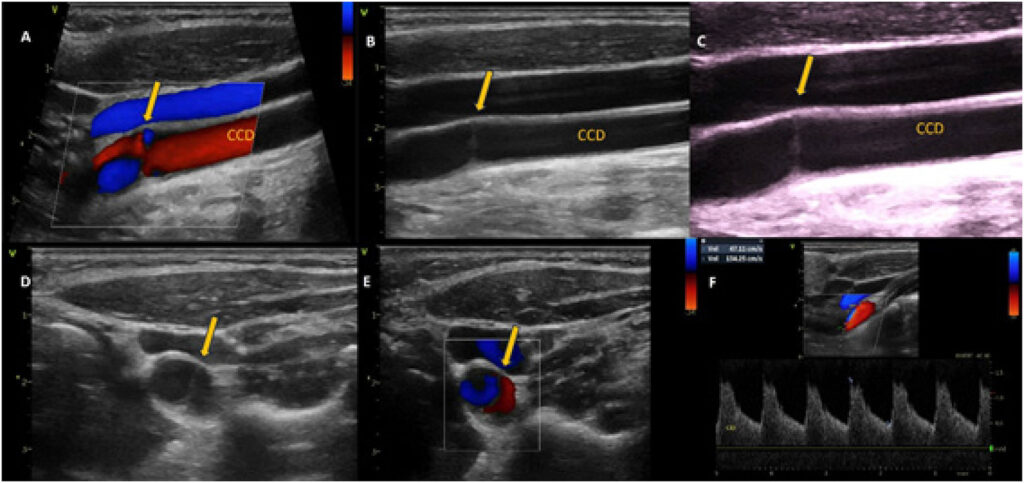

A Membrana Carotídea (MC) (carotid web) é uma doença não aterosclerótica da artéria carótida extracraniana, descrita como uma Displasia Fibromuscular (DFM) focal atípica, ainda pouco conhecida e diagnosticada. A MC tem sido relacionada à ocorrência de Acidentes Vasculares Encefálicos (AVE) e Ataques Isquêmicos Transitórios (AIT), acometendo pacientes jovens, sem outra etiologia identificada.

A Ultrassonografia no Diagnóstico da Membrana Carotídea: Relato de Dois Casos e Revisão da Literatura